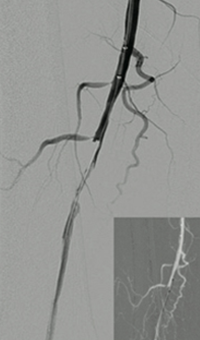

Thrombectomy of occluded SFA

Thrombectomy of Occluded SFA - pre-procedure

Imaging SFA showing thrombus and calcification

Male in his late 40s presenting with pain in his right leg. An angiogram showed a total occlusion in the right superior femoral artery (SFA)

Thrombectomy of Occluded SFA - catheter positioning

Solent™ Proxi catheter positioned before the lesion

The physician delivered (antegrade) the Solent Proxi catheter to the proximal margin of the occlusion

Thrombectomy of Occluded SFA - thrombus removed

Thrombus removed following AngioJet™ treatment

After the third pass with Solent Proxi

Thrombectomy of Occluded SFA - post-adjunctive treatment

Post-adjunctive treatment

Final angiogram showing flow post-treatment

Results from case studies are not necessarily predictive of results in other cases. Results in other cases may vary.